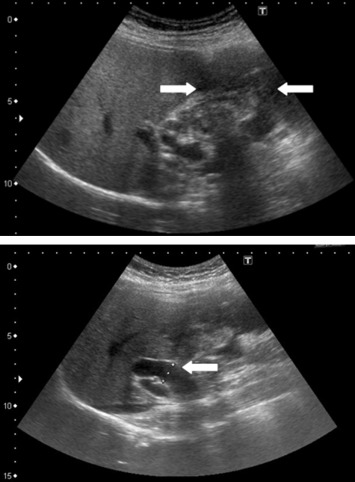

A 52-year-old female patient presented with postprandial epigastric pain that had persisted for 1 year. The pain was mild and improved after antacid treatment. She was seen at our hospital after being diagnosed with a hepatic tumor at a local clinic. Abdominal ultrasonography revealed one mixed echogenic tumor approximately 9.5 cm from the gallbladder sac and extending to S4–5 of the liver. The common bile duct was dilated to 1.4 cm (Fig. 1). Liver function tests and total bilirubin levels were within the normal range. However, carbohydrate antigen 19-9 (CA 19-9) was elevated to 60.9 U/mL. A follow-up abdominal computed tomography (CT) confirmed a 7.5 cm sized gallbladder cancer with liver invasion (Fig. 2), consistent with clinical Stage III cancer according to the TNM system (tumor-node-metastasis classification system).

Figure 1. Abdominal ultrasonography showing one mixed echogenic tumor approximately 9.5 cm from the head of the gallbladder sac. The common bile duct was dilated to 1.4 cm. |